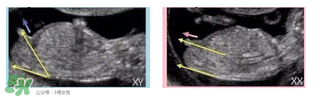

必須要NT超圖全景,可以看到下半部分的B超圖片才能判斷。外國(guó)人稱(chēng)這種判斷法為nub theory。

主要通過(guò)尾椎那里判斷。 為了讓大家更直觀(guān)一些,我找兩個(gè)比較明顯的圖,男左女右,大家看男孩兒的特征點(diǎn)與身體呈45度角,還多一些,而女孩兒的特征點(diǎn)幾乎和軀體平行。圖第一張男寶,第二張女寶

用線(xiàn)條表示一下就更直觀(guān)了.當(dāng)然,這也不是完全絕對(duì)的,如果你們發(fā)現(xiàn)自己的寶貝兒與心想的不一樣,那這理論不一定對(duì),不是絕對(duì)的.千萬(wàn)不要因?yàn)檫@個(gè)而影響自己孕期心情,寶寶健康是第一位的,我只是把自己所了解到的知識(shí)給大家普及一下。